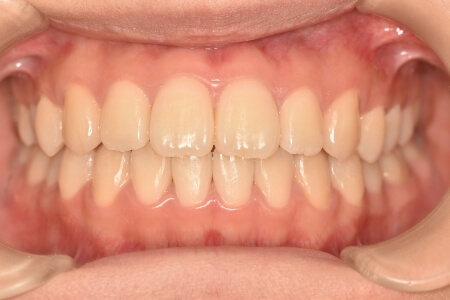

動的治療終了時

症例 症例 症例 症例 症例

治療としては、非抜歯の上、マウスピース型矯正装置(インビザライン)で配列を行いました。顎間ゴムの協力もあり、開咬、中心のズレがきれいに改善されました。

治療期間は、2年でした。